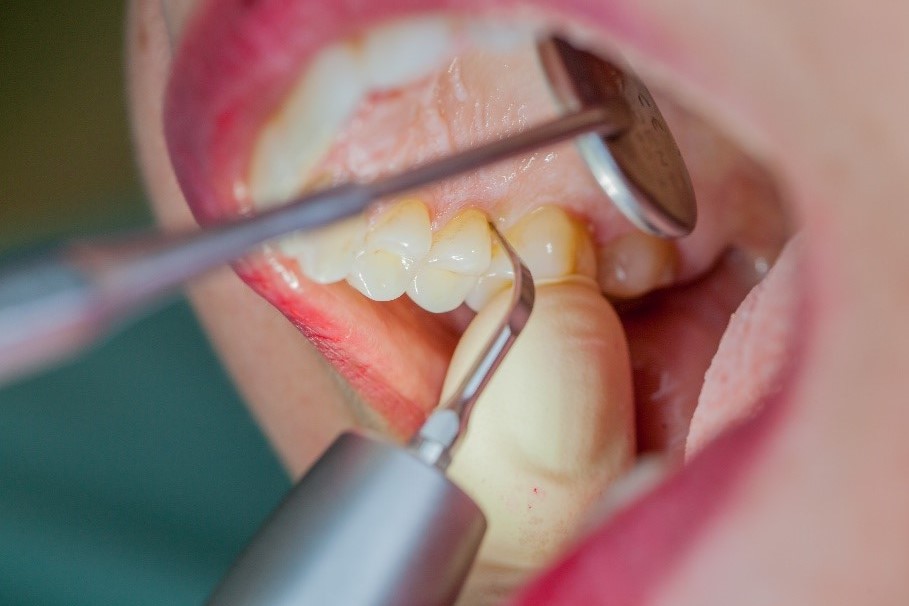

Removal of subgingival coatings (debridement) is carried out using sonic or ultrasonic devices and special periodontal tips as initial periodontal treatment (Fig. 3). Manual instruments can also be used. Further surgical and/or regenerative measures may be necessary, depending on the situation.

Sonar technology, W&H Proxeo with 1AP tip

Fig. 3: If marginal periodontitis is diagnosed, the initial debridement can be carried out very efficiently with an air scaler (sonar technology, W&H Proxeo with 1AP tip)